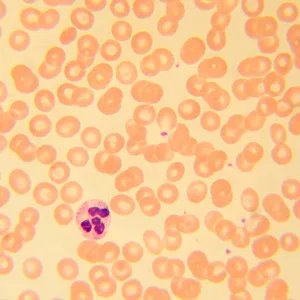

MAGUS Bio 230T – биологический тринокулярный микроскоп для лабораторных и исследовательских наблюдений в медицине, фармацевтике, криминалистике, биотехнологии и других областях науки. Применяется для работы с плоскими полупрозрачными и прозрачными образцами биологического происхождения: тонкими срезами и мазками. Оснащен ахроматической оптикой и галогенной подсветкой, наблюдения ведутся в проходящем свете в светлом поле. Микроскоп рассчитан на установку дополнительных аксессуаров для использования большего количества методов наблюдений: темного поля, фазового контраста, поляризованного света.

Чтобы расширить возможности микроскопа MAGUS Bio 230T, достаточно дооснастить его аксессуарами. Доступны окуляры и объективы, цифровые камеры и калибровочные слайды, конденсоры темного поля, устройства для наблюдений в поляризованном свете и с использованием фазово-контрастной микроскопии.